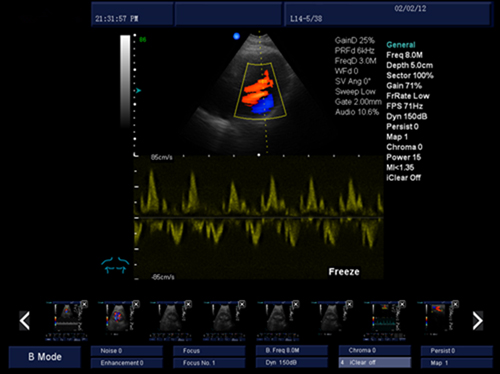

三同步顯示:二維、彩色和頻普三種模式同時(shí)處于實(shí)時(shí)狀態(tài),方便醫(yī)生對(duì)比觀察和定位取樣。 諧波成像:組織諧波成像使圖像更光滑、柔和、清晰,提升臨床診斷組織鑒別。